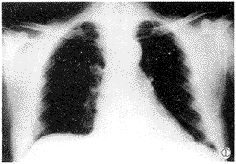

放射学实践990231 男性患者,50岁。因咳嗽3周伴脓痰1周入院。咳嗽呈阵发性,伴大量脓痰,并有胸痛、气喘、胸闷等。在当地医院抗炎无好转,脓痰转为白粘痰。入院体检及心电图、B超、肺功能检查均无异常。胸片见右肺门区一圆形高密度影(图1)。CT见病灶位于右下叶背段,大小约2cm×2cm,密度均匀,边缘光滑锐利、似有分叶,肺窗见单支血管供血(图2)。MRI见肿块呈等T1、等T2信号,肺门、纵隔未见肿大淋巴结(图3)。诊断:右下叶背段肿瘤性病变。

图1 胸部正位片:右肺门区一圆形高密度影。